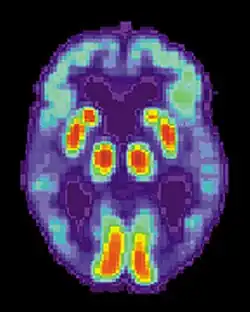

PET normal brain

PET Alzheimer's disease

Successful remembering involves recognition that something is familiar and recall of the context in which it was previously experienced. With age, the ability to discriminate between new and previous events begins to fail, and errors in recalling experiences become more common.[35] Larry Jacoby of New York University (1999) demonstrated how common these errors can become, lending a better understanding to why recognition errors are particularly common in Alzheimer's disease. In Jacoby's study, participants were given two lists of words: one to read and one which they would hear read aloud. All subjects were then given a "test" list which contained some words they had read, some they had heard, and some novel words; the subjects had to determine which words were which.[35] Jacoby found that university students and 75-year-olds were equally likely to correctly recognize whether or not the word had been presented, but 75-year-olds were much more likely to mistake whether the word was spoken or read. In other words, while recognition of familiar versus novel words remained relatively stable across age groups, source confusion increased dramatically with age.